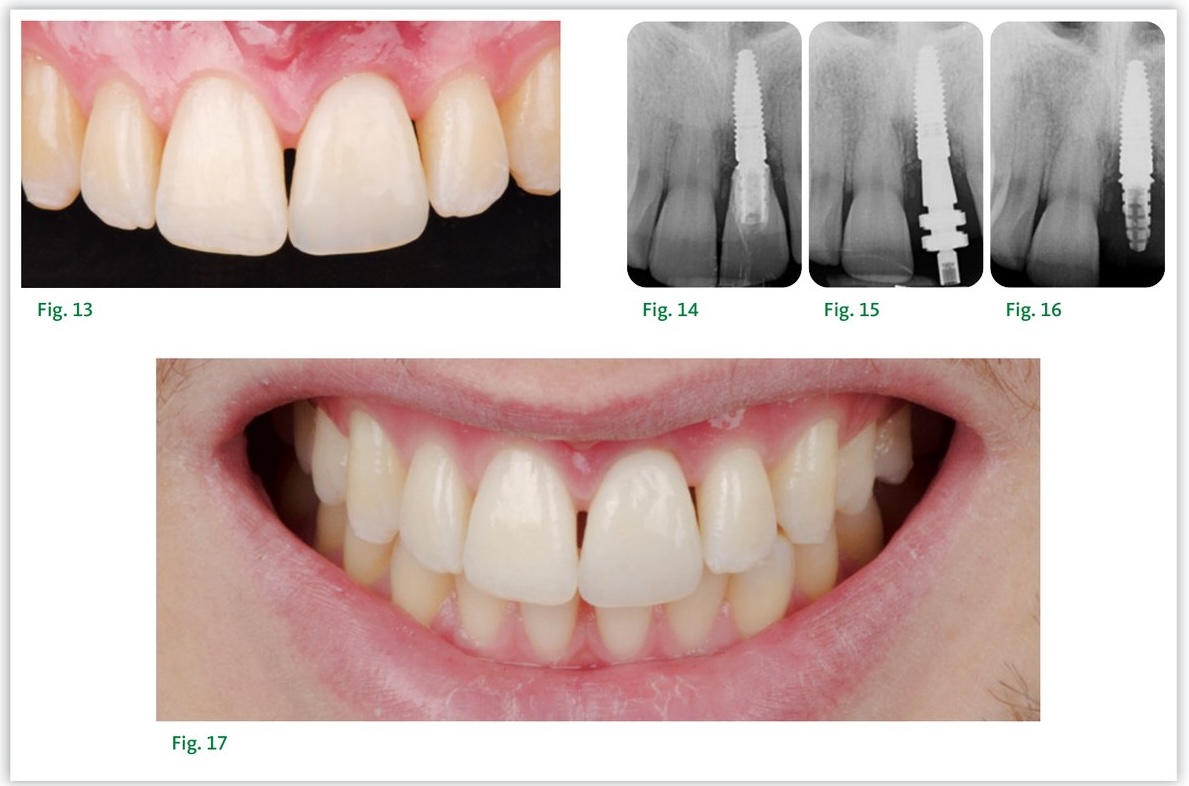

Le pilier provisoire est mis en place et son bon positionnement est vérifié par radiographie rétro-alvéolaire. L'alvéole est protégée par un morceau de feuille de digue, et une coque provisoire en résine réalisée à partir du wax-up est positionnée. L'injection de résine liquide permet de solidariser le pilier provisoire à la couronne provisoire.

L'ensemble est dévissé et, hors de la bouche, le profil d'émergence de la couronne provisoire est préparé — parfaitement concave depuis la base du pilier jusqu'à la position du collet gingival. L'espace entre l'implant et la corticale vestibulaire est comblé avec un matériau xénogène à faibles propriétés de résorption, selon le principe de la Dual Zone. La couronne provisoire est ensuite vissée et serrée à 35 N.cm.

Solidarisation de la couronne provisoire, comblement à la xénogreffe et résultat postopératoire

Résultat à 3 mois — restauration implantaire définitive en secteur antérieur